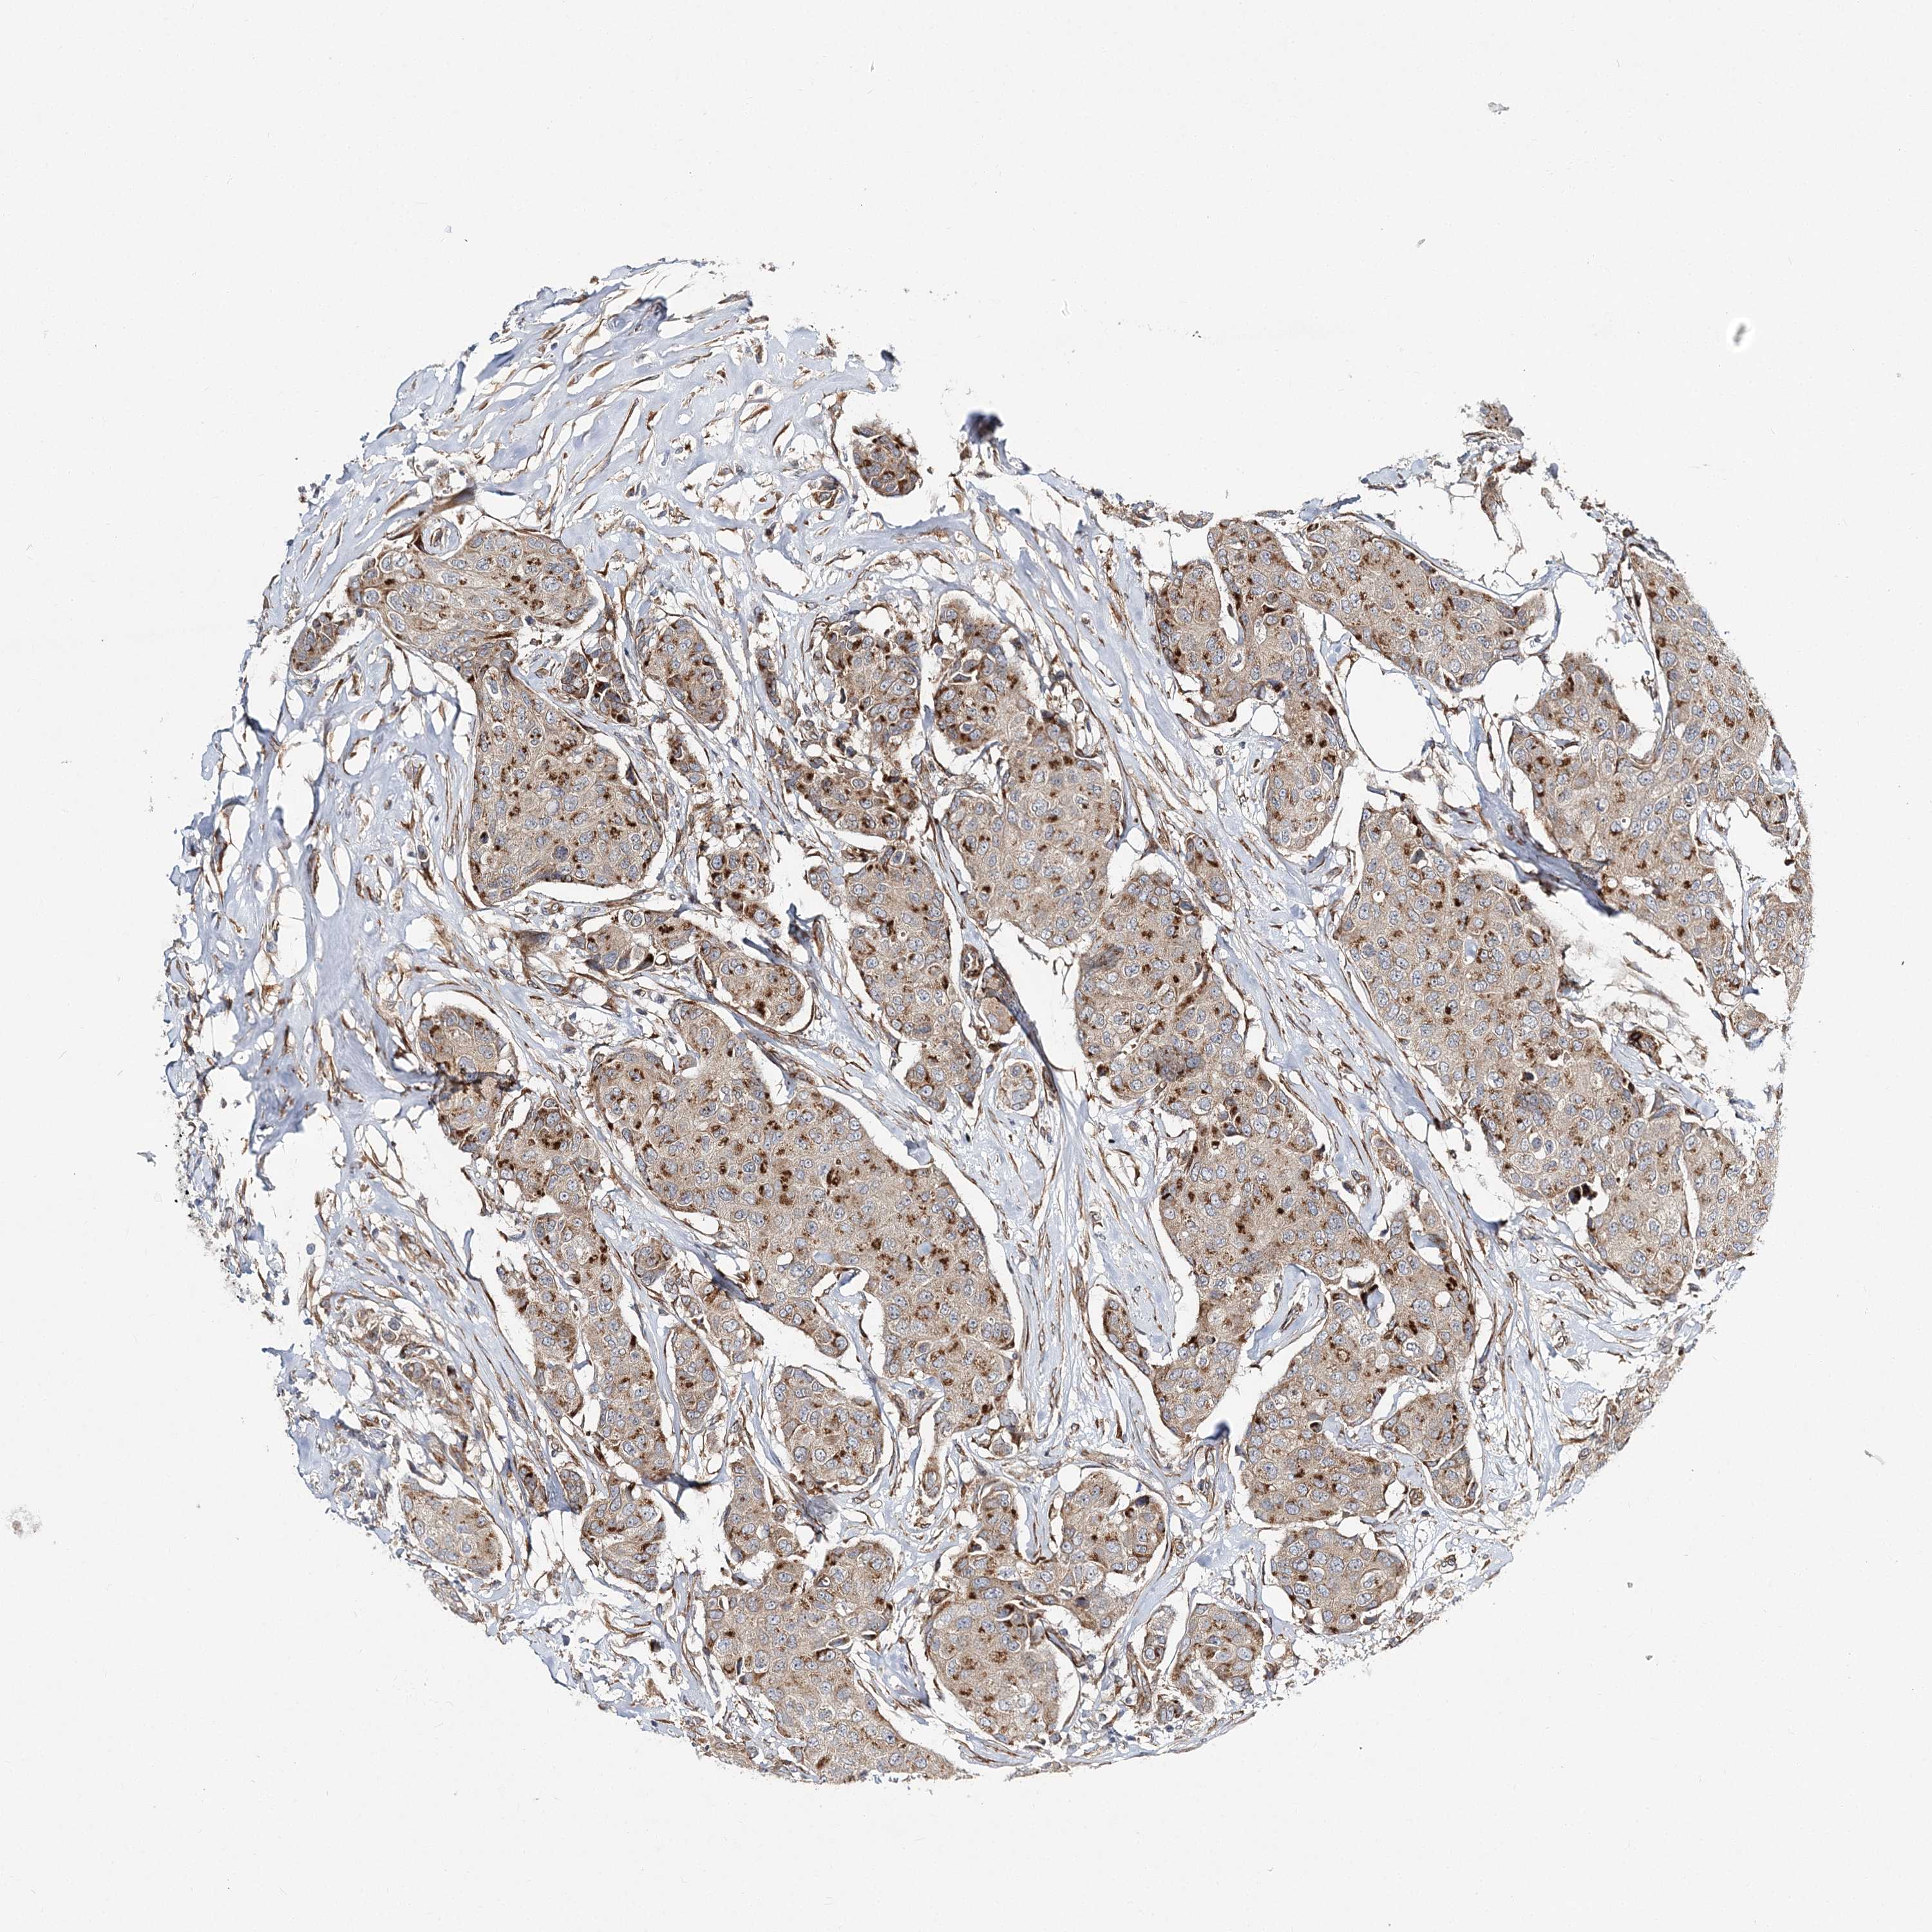

CANCER BREAST CANCER Show tissue menu

BRCA TCGA BRCA VALIDATION PROTEIN EXPRESSION